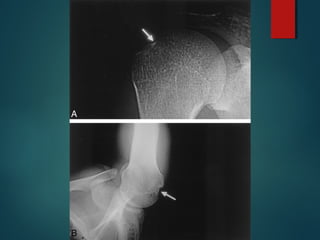

Frequently, patients with recurrent dislocations have

bony deficits in one or both of these surfaces.

Glenoid Bone loss

Hill Sach Lesion